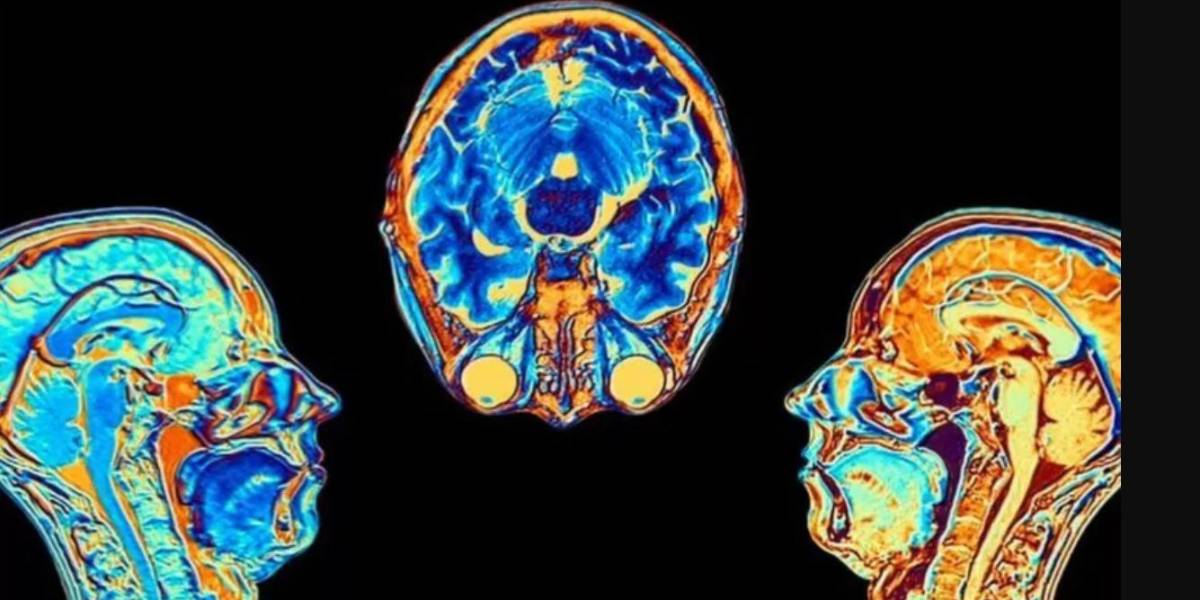

Contagiarse de covid-19 puede provocar cambios en el cerebro, según indicó un estudio publicado en la revista Nature.

Los investigadores hallaron diferencias significativas en las resonancias magnéticas hechas antes y después de la infección.

Incluso después de una infección leve, las imágenes mostraron que el tamaño total del cerebro se había reducido ligeramente, con menos materia gris en las regiones relacionadas con el olfato y la memoria.

Escán

FUENTE DE LA IMAGEN,UK BIOBANK

Pie de foto,

Los investigadores no sabe si los cambios se revierten con el tiempo.